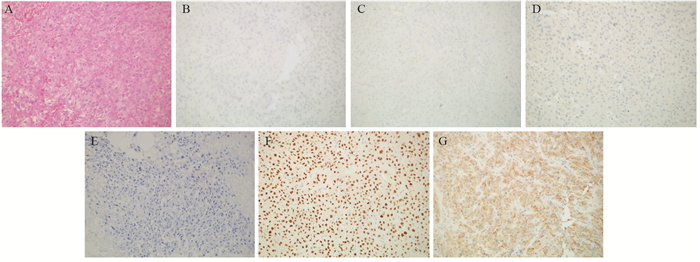

在ST-PACS医学图像工作站(北京思创贯宇科技开发有限公司)上选取肿瘤最大层面相邻的三个层面,利用自由形标记工具在ADC图上手工绘制ROI,在b=1 000s/mm2下测量平均ADC值(ADCmean)、最小ADC值(ADCmin),每个层面测量3次,并计算平均值。相对ADC值(rADC)=瘤体区ADC值/对侧脑白质ADC值,见图 1。

![]() 图 1 少突胶质细胞瘤(WHOⅢ级;IDH-1突变/1p19q共缺失)MRI和病理学表现Figure 1 MRI and pathological manifestations of oligodendrocytoma (WHO gradeⅢ) with IDH-1 mutation/1p19q co-deletionA, B: the lesions in the right temporal-parietal lobe showed heterogeneous low signal and high signal on T1WI and T2WI, respectively; C, D: DWI presented as an inhomogeneous equal-slightly higher signal (mild diffusion restricted) (C) and ADC map showed an inhomogeneous low-slightly higher signal (D); E: the measurement method of ADC value to select three ROI (10-20 mm2) in lesions and take their average values as well as select the contralateral normal brain white matter to calculate rADC; F: tumor cells were arranged in diffuse pieces, the nucleus with obvious atypia was large, and numerous necrotic regions were found in the lesions (HE ×200).

图 1 少突胶质细胞瘤(WHOⅢ级;IDH-1突变/1p19q共缺失)MRI和病理学表现Figure 1 MRI and pathological manifestations of oligodendrocytoma (WHO gradeⅢ) with IDH-1 mutation/1p19q co-deletionA, B: the lesions in the right temporal-parietal lobe showed heterogeneous low signal and high signal on T1WI and T2WI, respectively; C, D: DWI presented as an inhomogeneous equal-slightly higher signal (mild diffusion restricted) (C) and ADC map showed an inhomogeneous low-slightly higher signal (D); E: the measurement method of ADC value to select three ROI (10-20 mm2) in lesions and take their average values as well as select the contralateral normal brain white matter to calculate rADC; F: tumor cells were arranged in diffuse pieces, the nucleus with obvious atypia was large, and numerous necrotic regions were found in the lesions (HE ×200).1.4 统计学方法